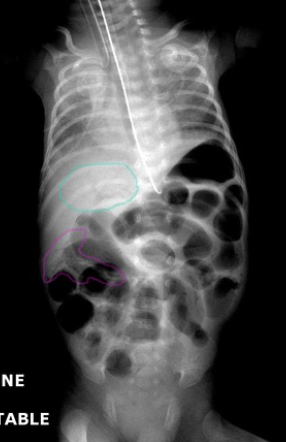

Q

Dilated bowel loops on abdominal x-ray, pneumatosis and portal venous air

What is the most important test for diagnosing necrotising enterocolitis?

Abdominal x-ray, repeated seially every 6 hours until definitive treatment - Dilated loops of bowel - Pneumatosis intestinalis (pathognomic) - Portal venous air (poor prognostic sign) (Diagnostic findings)